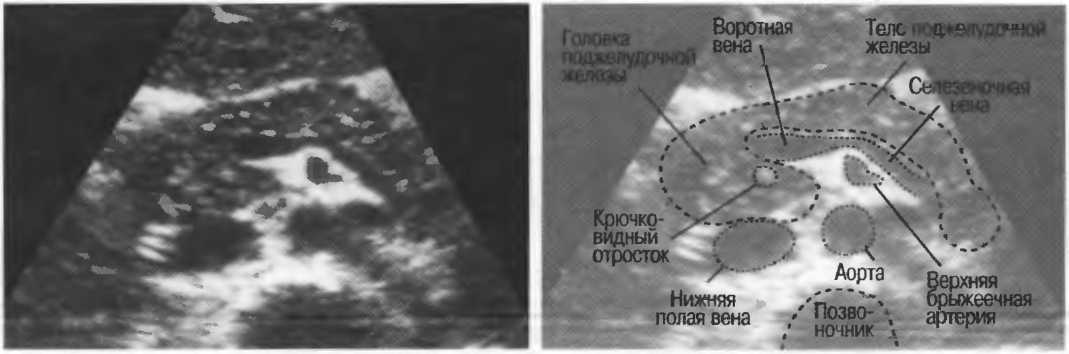

2. Верхняя брыжеечная артерия должна визуализироваться в виде округлого или овального эхонегативного образования, расположенного рядом с поджелудочной железой у здорового взрослого обследуемого (рис. 24). Наиболее простым способом проверки качества изображения является визуализация своей собственной верхней брыжеечной артерии. Сохраняйте эхограммы после каждого исследования для сравнения.

Рис.24. Поперечный срез: верхняя брыжеечная артерия представлена эхонегативным округлым образованием, окруженным эхогенной жировой клетчаткой, расположенным близко к поджелудочной железе.